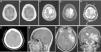

ResultsOur AG patients correspond to 2.5% of the central nervous system tumor patients evaluated in our institution. The mean age at presentation was 25.7 years, with a male predominance. The most common clinical presentation was generalized tonic–clonic seizures (3/7 cases), in correlation with frequent cortical/subcortical location (6/7 cases). Histopathologically, all our cases showed high-grade features in glial (glial fibrillary acid protein-positive) and neuron-ganglion cells (synaptophysin, PGP-9.5, neurofilament, NSE and CD56-positive), as well as moderate cellularity, frequent mitotic figures and a Ki-67 labeling index >5%. All our patients had poor survival.

ConclusionWe found that a typical histopathological and immunohistochemical profile is constant and can be useful in early diagnosis of these aggressive neoplasms.